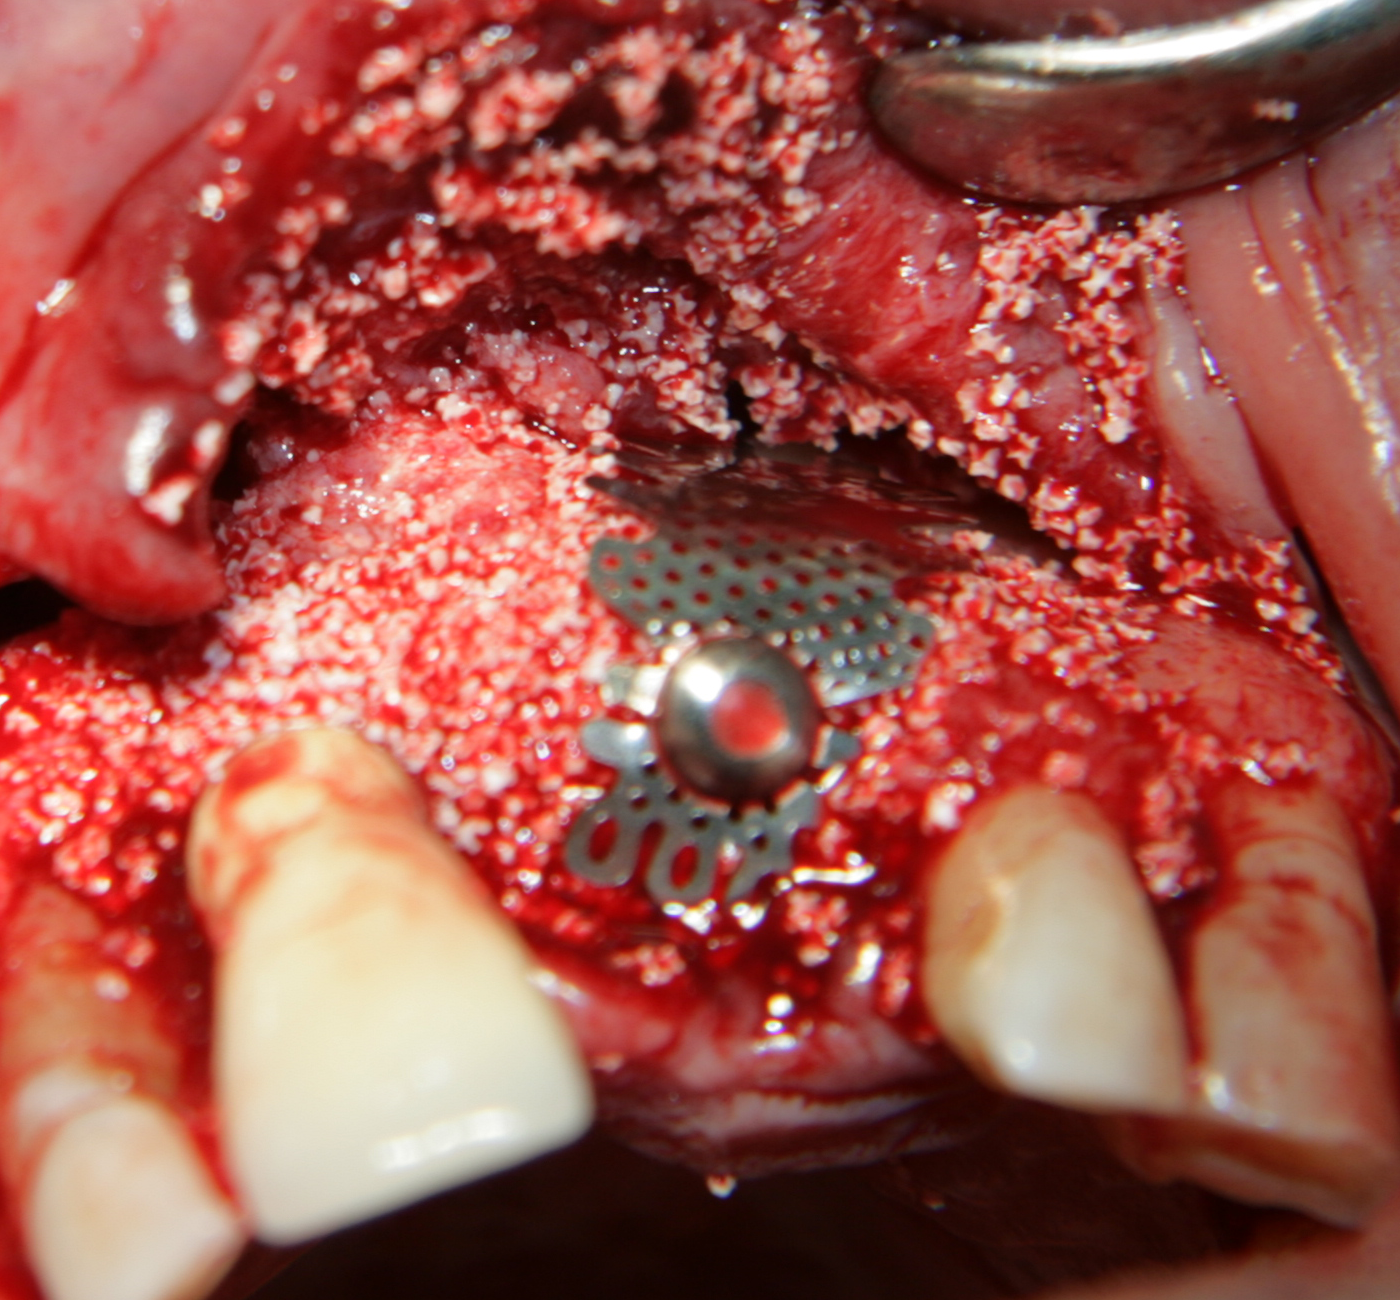

Аплициран е костозаместващ материал -

Kasios (Франция)

Костозаместителят е покрит с

титанова мрежа. Тя има полезен ефект - запазва формата на графта и

предпазва меките тъкани от колапс. По този начин се осигурява един стабилен

обем, който да се изпълни с костна тъкан. При липса на

титановата мрежа меките тъкани колабират, което е съпроводено със

значителна редукция на пространството за образуване на нова костна тъкан.

Важно е мрежата да бъде имобилизирана - всяка подвижност води до

костна резорбция на младата костна тъкан, съответно до опорочаване на

резултата от лечението.

Доскоро имобилизацията се осъществяваше с дебел конец, който захваща

свободния край на мрежата към вътрешната повърхност на периоста; от 2012

година обаче Neobiotech въведе т.нар.

GBR-kit, с помощта на който мрежите се фиксират с

различни по диаметър и дължина винтове.

Титановите мрежи дават много добър резултат при имедиатно поставяне на

зъбни

импланти след екстракция на зъби.